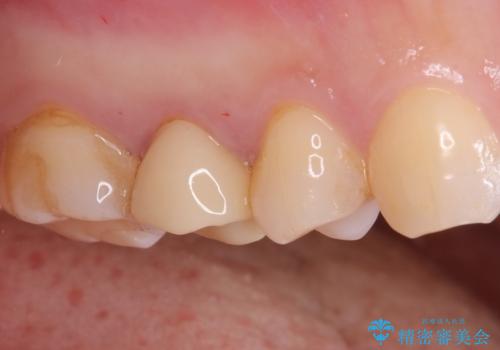

【オールセラミッククラウン】根管治療も行いたい。

- 右上の歯が、噛むと痛いことを主訴に来院されました。

ラバーダムと顕微鏡を用いた根管治療を希望され、治療後は痛みも改善することができました。

その後、オールセラミッククラウンにて修復を行っています。

顕微鏡を用いて根管治療を行うことで、破折の有無などを判断しやすくなります。